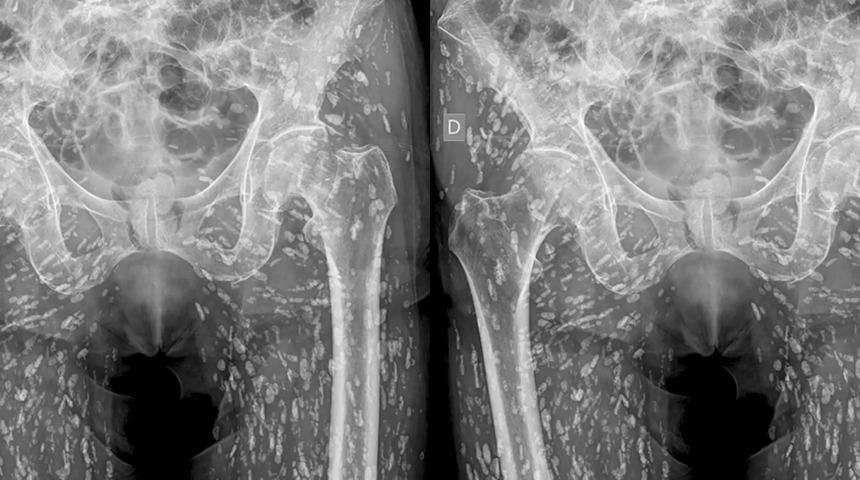

Kardiyovasküler acil durumlar ve acil radyoloji konusunda uzmanlaşmış bir acil servis doktoru olan Sam Ghali, yakın zamanda bir hastanın pelvik bölgesinin vücudunun yüzlerce beyaz noktayla dolu olduğunu gösteren sıra dışı röntgen görüntüsünü paylaştı.

Bunların hepsi, alt vücudunun yumuşak dokularına sıkışmış kireçlenmiş tenya yumurtalarıydı. İlginç bir şekilde, hasta sistiserkozu hakkında hiçbir şey bilmiyordu ve bunu ancak düştükten ve kalça ağrısı yaşadıktan sonra röntgen çektirmeye geldiğinde öğrendi.

Ghali, X (Twitter)'da "Bu, kistiserkoz olarak bilinen bir durumdur, esasen bunlar taenia solium'un larva kistleridir, ayrıca domuz tenyası olarak da bilinir. Bu kistler vücudun her yerine, özellikle kalçaların ve bacakların kas ve yumuşak dokularına yayılabilir." dedi.

Bu kireçlenmiş yumurtalar beyne ulaşmadıkları sürece temelde zararsızdır, artık canlı değillerdir; ancak yüzlerce pirinç tanesi benzeri kistlerle karşılaşma düşüncesi bile akıl almaz geliyorsa, tedbir amaçlı çiğ veya az pişmiş et ve balık tüketmekten uzak durmalısınız.